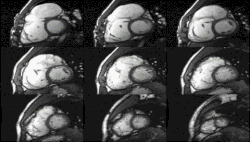

Heart function using cine imaging

Functional and structural information is acquired using bSSFP cine sequences. These are usually retrospectively-gated and have intrinsically high contrast in cardiac imaging due to the relatively high T2:T1 ratio of blood compared to myocardium. Images are typically planned sequentially to achieve the standard cardiac planes used for assessment. Turbulent flow causes dephasing and signal loss allowing valvular disease to be qualitatively appreciated. The left ventricular short axis cines are acquired from base to apex and are used for quantifying end-diastolic and end-systolic volumes, as well as myocardial mass. Tagging sequences excite a grid pattern that deforms with cardiac contraction allowing strain to be assessed.